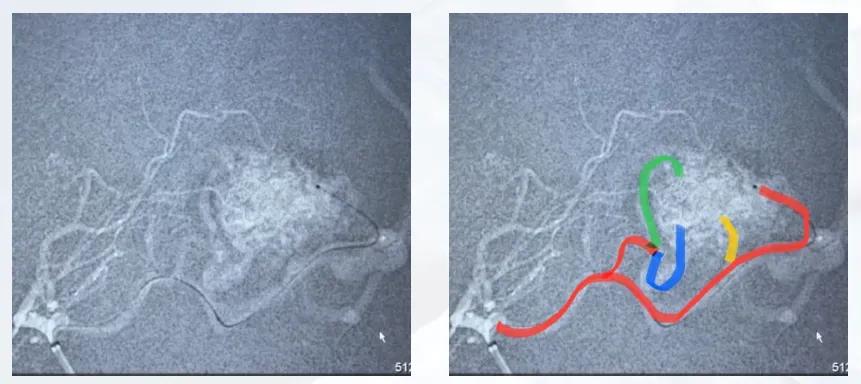

患者因突发意识不清、肢体抽搐2 h入院,中度昏迷状态,气管插管,双侧病理征阳性,头颅CT提示顶枕叶大量出血并破入脑室。入院后开通绿色通道,行急诊脑室外引流降低颅内压。血管造影提示病变由大脑后动脉多支供血,存在皮层静脉向矢状窦引流及深静脉引流,可见明显静脉湖。

图2 患者血管造影图

图3 脑动静脉栓塞-液态栓塞

图4 血管内治疗过程

治疗策略:采取“介入栓塞+神经内镜血肿清除+伽马刀放疗”的多阶段联合治疗。首先对大脑后动脉4支供血分支行介入栓塞,术中确保畸形团内安全栓塞,避免反流,栓塞后畸形团基本闭塞,仅深部少量可疑残留且流速流量极低;随后行神经内镜下单纯血肿清除,术后颅内情况稳定;术后两周造影复查见深部残留畸形显影,因残留病灶小于3 cm,予伽马刀放疗。